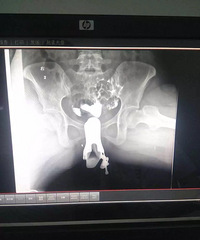

做了输卵管造影检查 医生只给开了一大堆药 有懂的人吗?